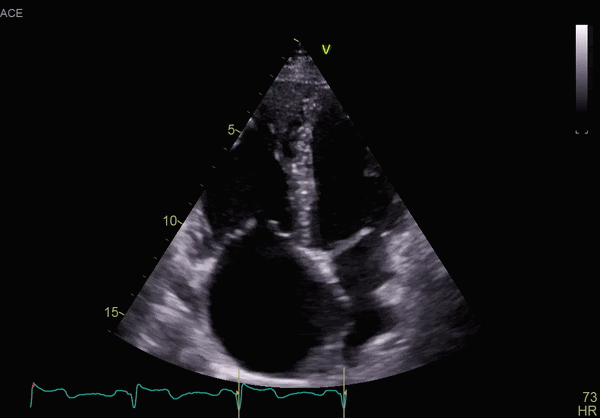

Systolic dysfunction of left and right ventricle

Left ventricular function assessment

Right ventricular function assessment